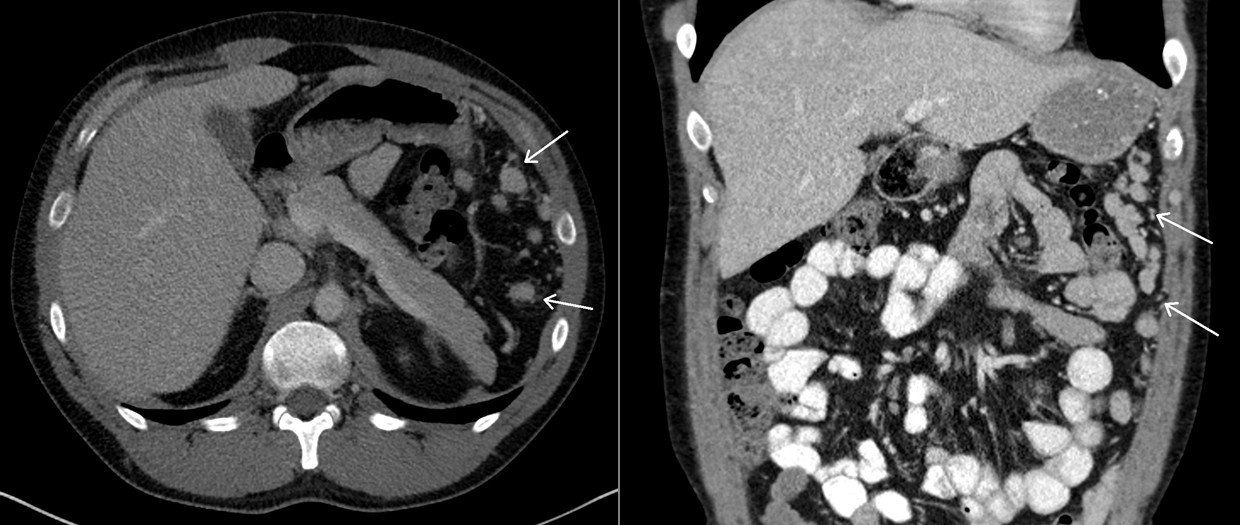

A 25-year-old man presents with complaints of generalized fatigue and abdominal discomfort. The patient was diagnosed with Epstein-Barr virus infection, and CT was performed for the abdominal discomfort. The patient has a remote history of a motor vehicle collision, which required abdominal surgery. Axial and coronal images from the CT scan are shown below (areas of interest denoted with arrows).

What is your diagnosis?